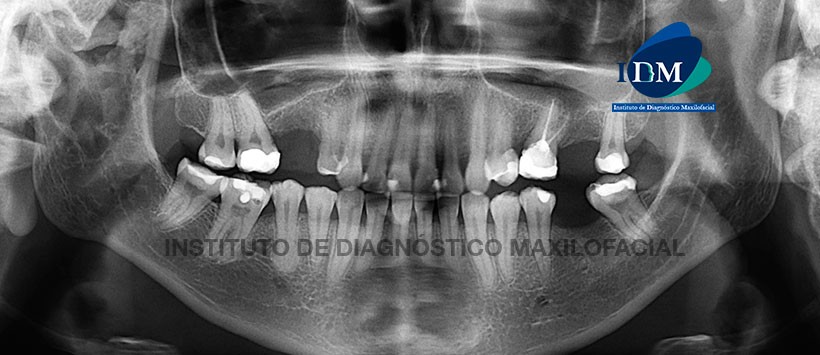

En la radiografía panorámica, se pudo observar la neumatización alveolar de ambos senos maxilares, múltiples restauraciones y ausencias de piezas dentarias así como la presencia de material de obturación en la pieza 26. Sin embargo lo más resaltante es la presencia de una imagen radiolúcida localizada en cuerpo, cóndilo y apófisis coronoides de lado derecho, de forma irregular, con límites definidos y parcialmente corticalizados. (Figura 1)